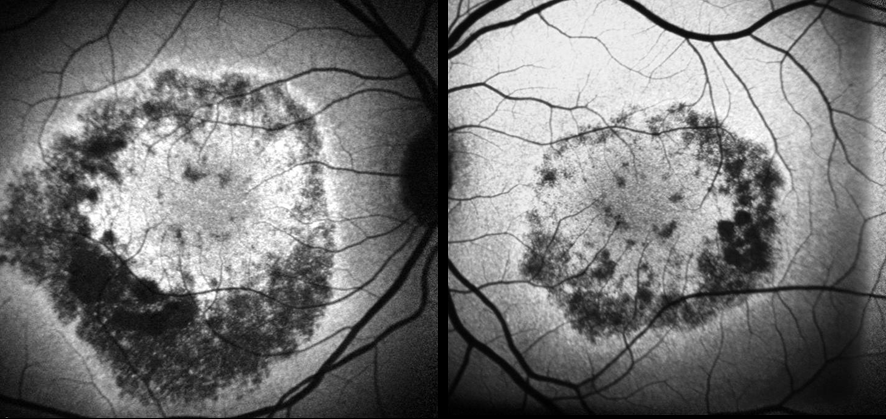

Fluorescein Angiography (FA) showed early annular hyperfluorescence consistent with bull’s eye maculopathy in both eyes (Figure 2 [Fig. 2]). SD-OCT of the macula showed retinal thinning (central foveal thickness 160 µm and 159 µm in the right and left eyes, respectively). Autofluorescence imaging showed an area of annular hypoautofluorescence congruate with the epithelial defects seen on FA (Figure 3 [Fig. 3]). The full-field ERG was normal for both cone and rod responses.

Figure 2: Fluorescein angiogram showing annular window defect in both eyes

Figure 3: Fundus autofluorescence showing areas of marked hypoautofluorescence congruent with RPE changes